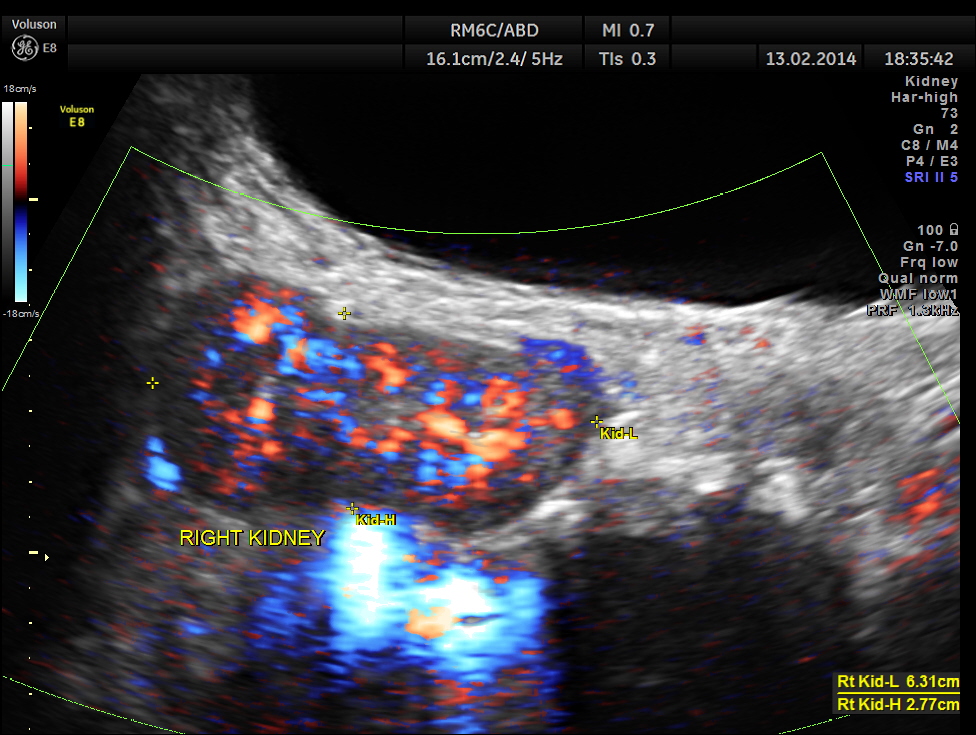

The following are the pictures of the kidney , which show the congenital horse shoe kidneys , placed ectopically in the pelvis. He had no urinary symptoms or low back ache at any time .

The right and left portions of the horse shoe are shown separately below

The power doppler pictures are given below.